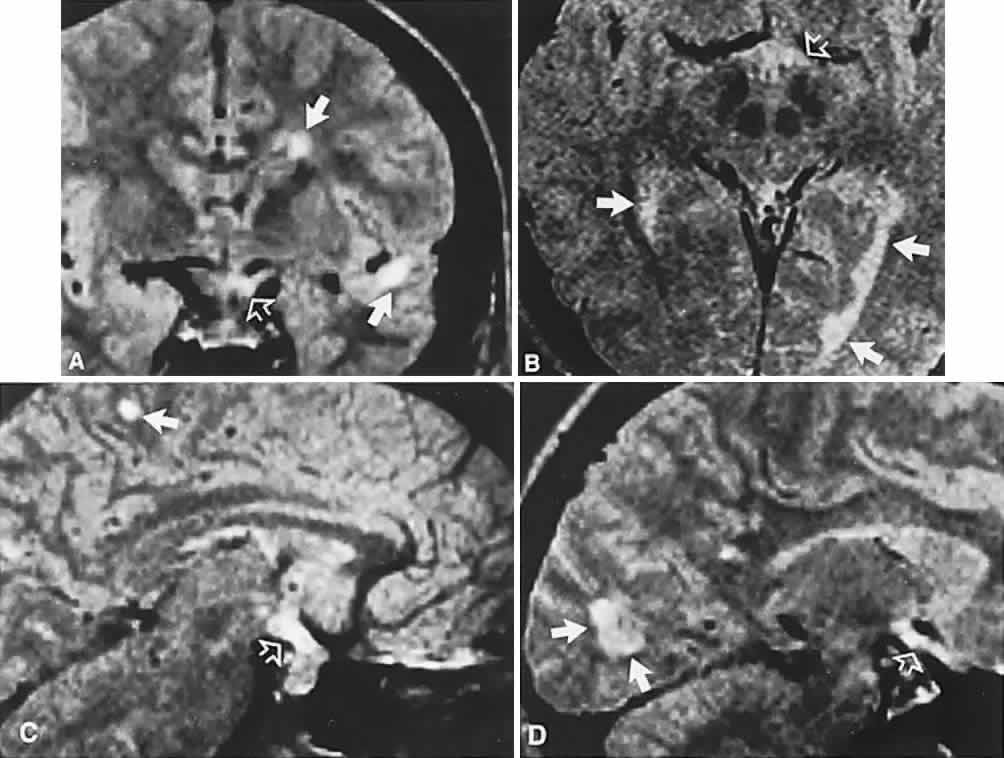

Endocrine-inactive tumors fail to produce clinical manifestations of any secretory product when a normal hormone is produced in amounts too small to be detected, when an abnormal hormone is produced but not recognized by biologic receptor sites or detected by radioimmunoassay, or when formerly endocrine-active cells have lost the ability to produce hormone as a result of degeneration. Of 1000 pituitary tumors surgically treated by Wilson,20 226 were endocrine-inactive, and 774 were secretory, as follows: PRL, 410; GH, 195; ACTH, 167; thyroid-stimulating hormone, 2. Nonsecretory adenomas, which consist mostly of null-cell adenomas, tend to be larger at presentation than do secretory tumors, with a median age of 57 years, and male predominance.21 Nonocular symptoms, as previously discussed, include chronic headaches (severe or mild) in more than two-thirds of patients,1 fatigue, impotence or amenorrhea, sexual hair change, or other signs of gonadal, thyroidal, or adrenal insufficiency. The typical sequence of hormonal deficiencies associated with large adenomas is early loss of GH and gonadotropin, later loss of thyrotropin and corticotropin. With the increasing application of neuroimaging and sensitive assays for abnormal hormones, the incidence of ophthalmologic presentation is decreasing, whereas the incidence of neuro-endocrine findings is increasing. Signs and symptoms, visual or otherwise, nonetheless may exist for months to years before so much as a visual field or plain skull film is obtained.4 Visual failure with pituitary tumors assumes a limited number of field patterns. As suprasellar extension evolves, a single optic nerve may be compromised, with resultant progressive monocular visual loss in the form of a central scotoma. More frequently, as the tumor splays apart the anterior chiasmal notch, superotemporal peripheral hemianopic defects occur. However, this well-touted superior bitemporal hemianopia is almost always accompanied by minor or major hemianopic scotomas approaching the fixational area along the vertical meridian (see Fig. 1). Asymmetry of field defects is the rule, the eye with the greater deficit likely showing diminished visual acuity. Marked asymmetry is not uncommon, such that one eye may be nearly blind while the other shows a temporal hemianopic defect (see Fig. 1C); this combination is as exquisitely localizing to the chiasm as is classic bitemporal hemianopia. Adenomas extending posteriorly produce incongruous hemianopias (see Fig. 5) by optic tract involvement; central vision is usually diminished, at least in the ipsilateral eye, and optic atrophy evolves. On extremely rare occasions, arcuate Bjerrum's scotomas extend from the blind spot into the nasal field22 or terminate at the vertical meridian.23 Such defects are usually monocular and are difficult to distinguish from glaucoma by perimetry alone. With progression, especially if the temporal field of the other eye becomes involved, a more typical field pattern evolves. In late stages of visual loss, the only suggestion of the chiasmal character of field defects may be minimal preservation of the nasal field of one eye (see Fig. 1C). The importance of serial examinations is obvious, but, when doubt exists, neuroimaging is mandatory. The absence of field defects, for example, in patients undergoing evaluation for amenorrhea, galactorrhea, or sellar enlargement incidentally discovered, does not imply the absence of an adenoma. Obviously, patients with microadenomas, that is, confined within the sella, do not have field defects. From a study24 of 50 cases of pituitary adenomas with chiasmal syndrome, it was concluded that visual disturbance occurs when the chiasm is displaced approximately 10 mm upward (see also Volume 2, Chapter 4, Fig. 6). The modern management of pituitary adenomas should involve several disciplines: current neuroradiologic studies detect microadenomas and provide precise delineation of gross morphology and status of neighboring structures, and mixed MRI signals suggest new or old hemorrhage, cysts, and so forth (Fig. 2); radioimmunoassay techniques assay PRL and other endocrine levels; oral neuropharmacologic agents, such as bromergocryptine, provide a “medical adenomectomy” for hyperprolactinemia and acromegaly; transsphenoidal surgery, including high-illumination microscopical procedures, televised radiofluoroscopic monitoring, and infection control, has all but replaced transcranial approaches; immunohistochemistry techniques have replaced the anachronistic tinctorial designations (e.g., chromophobe, basophilic) with a functional classification. PRL-secreting adenomas are the single most common type of pituitary tumor and occur more frequently in women than in men.20 Most of these tumors are microadenomas, although tumors confined to the sella are relatively rare in men. In women, amenorrhea and galactorrhea are the symptoms that provoke investigation, whereas in men, symptoms include loss of libido, impotence, gynecomastia, galactorrhea, and hypopituitarism.25 These various clinical manifestations occur with or without visual loss, depending on the volume of the adenoma; that is, the degree of suprasellar extension and compression of the chiasm. As a rule, true prolactinomas are associated with serum PRL levels higher than 150 to 200 ng/ml, and they usually range from 700 to 7000 ng/ml; the larger the tumor, the greater the serum PRL and, therefore, radiologically large adenomas with PRL levels lower than 200 ng/ml are probably nonsecreting and are not likely to respond to medical therapy (see below). Hyperprolactinemia up to 100 ng/ml may be due to simple physiologic causes, including stress, sexual intercourse, nipple stimulation, and exercise, or it may be secondary to pharmacologic agents such as phenothiazines, tricyclic antidepressants, calcium channel blockers, and cimetidine.25 However, other lesions in and around the pituitary gland and hypothalamus that compromise the pituitary stalk may present as “pseudoprolactinomas.” Immunohistochemical studies performed on 97 tissue specimens in patients operated on for presumed prolactinomas at the Mayo Clinic in Rochester, Minnesota26 revealed 65% to be microadenomas, but null-cell tumors accounted for 4 of 5 pseudoprolactinomas; these tended to be large at diagnosis, but with minor PRL elevation. Suprasellar cystic lesions can also cause hyperprolactinemia with field defects,27 as can carotid suprasellar aneurysms.28 Unlike true prolactinomas, non-PRL-secreting suprasellar tumors, with secondary hyperprolactinemia due to pituitary stalk compression, do not show a correlation between size and PRL level.29 With the advent of the ergot-derived dopamine agonist bromocriptine, there is a pharmacologic alternative (or adjunct) to surgery for prolactinomas. Bromocriptine (2-bromo-alpha-ergocryptine) is representative of a class of ergot derivatives that, since the early 1970s, have been known to inhibit pituitary gonadotropic function, reduce PRL secretion, and diminish the size of pituitary tumors (see Fig. 2). Such ergot derivatives are structurally related to dopamine, a PRL-inhibitory factor elaborated by hypothalamic dopaminergic neurons. It is likely that bromocriptine acts in two ways: dopamine turnover in tubero-infundibular neurons is depressed, thereby increasing hypothalamic dopamine; dopamine receptors of the pituitary are inhibited, reducing both spontaneous PRL secretion and the release of PRL provoked by thyrotropin-releasing hormone. At any rate, bromocriptine decreases PRL production and secretion, with resultant reduction in lactotrope size and subsequent diminution of tumor volume, often rapidly, within 1 to 2 hours of initiation of treatment.25 Spark and associates,30 among others, reported the efficacy of bromocriptine in reducing tumor size; it was demonstrated that bromocriptine lowered PRL, reduced GH in acromegaly, and reversed visual field defects. However, patients with extrasellar extension or with high PRL levels did less well. The great weight of evidence now clearly shows that most microadenomas (intrasellar) are demonstrably reduced in size,31 in about 3 months at an average dose of 5 mg per day, but cystic necrosis may develop, and adenomas may increase in volume if bromocriptine is discontinued. The tumor-reducing effect of bromocriptine on prolactinomas has been tested on 5 types of large, extrasellar pituitary tumors.32 Twenty patients were treated prospectively for up to 4.5 years with bromocriptine 30 mg or 60 mg per day (2 patients received 15 mg and 160 mg, respectively), and the effect on the size of the pituitary tumors was quantitated by planimetry of CT scans before and during treatment. The immediate success rate was 16 of 20 tumors, and 11 nonsecreting tumors were reduced by a median of 32%, with an immediate success rate of 9 of 11. Nine secreting tumors (4 that secreted PRL; 3, GH; 1, ACTH; and 1, thyroid-stimulating hormone) were reduced by a median of 51%. The reduction in tumor size was significantly associated with pretreatment volume, but not with the hormonal serum concentrations or with previous radiation treatment. Moreover, bromocriptine treatment did not cause any pituitary insufficiency other than the desired suppression of PRL. The clinical course of 10 patients with macroprolactinomas at the Wills Eye Hospital in Philadelphia was carefully documented33 after treatment with bromocriptine in daily doses ranging from 7.5 to 30 mg. Nine patients enjoyed improvement in acuity and fields quite rapidly, often within a few days, including the following: hand movements to 20/20 within 1 month, counting fingers to 20/20 or 20/30 within 7 to 12 days, and dramatic recovery of field defects. There was also a demonstrable decrease in tumor size by CT criteria, and lowering of serum PRL. Four patients subsequently required transsphenoidal decompression, for conditions including failure of visual improvement, cerebrospinal fluid (CSF) rhinorrhea, and medication intolerance. The authors cautioned that the long-term effects of bromocriptine therapy are not known, and prompt tumor regrowth is to be anticipated when the drug is discontinued. It was recommended that patients who are to undergo surgical decompression should be treated preoperatively to decrease tumor size and “to facilitate surgical removal,” and that residual tumor with elevated PRL should be treated with bromocriptine. A similar patient34 with a large pituitary tumor, hyperprolactinemia, bitemporal fields defects, and invasion of one cavernous sinus (involving the fifth and sixth cranial nerves) was treated with bromocriptine 7.5 mg per day,35 with marked reduction in the tumor size and resolution of field defects and cranial nerve dysfunction over a 6-month period, at which point the sella appeared empty. Other dopamine agonists are available or under investigation, including long-acting bromocriptine (Parlodel), cabergoline, and CV-205-502; some prolactinomas resistant to standard dopamine agonists may respond to more potent agents such as cabergoline.35 Ophthalmic results in patients with macroprolactinomas treated with dopamine agonists show generally good results, with few instances of pituitary necrosis.25,36 Indeed, it may be that these newer pharmaceuticals should be the treatment of choice in patients with large pituitary tumors with extrasellar extensions. These unquestionable successes notwithstanding, there remain unanswered questions concerning dopamine agonist therapy: Is long-term medical therapy preferable to simple transsphenoidal surgery? Can such patients ever be weaned from medical therapy? What about the ultimate outcome of tumors not characterized by PRL secretion? Should large, asymmetric (invasive?) adenomas be pretreated to make surgical removal easier? Based on an extensive experience, Wilson20 recommended microsurgical transsphenoidal removal of macroprolactinomas, with presurgical bromocriptine treatment of tumors larger than 2 cm. The details of neurosurgical procedures are beyond the scope of this present work, but Wilson's review and other sources37 should be consulted. Varying within the spectrum of surgical experiences, complications of transsphenoidal procedures include anterior pituitary insufficiency (about 20%), diabetes insipidus (about 18%), CSF rhinorrhea (about 4%), and, rarely, loss of vision or diplopia.38 Infrequent untoward results include hydrocephalus secondary to subarachnoid blood, cerebral ischemia related to vasospasm, meningitis with or without CSF leak, and death associated with intraoperative or postoperative hemorrhage.20,38 Radiation therapy is currently used as an integral part of postoperative treatment in patients with incompletely resected nonfunctional adenomas. External-beam conventional protocols delivering median total dosage of 45 Gy are considered highly effective in preventing recurrence of hormonally inactive tumors, but they may compound relative hypopituitarism.39 Young patients with total tumor removal, or without MRI evidence of recurrence, may be safely observed with radiation therapy held in reserve. The role of stereotactic radiosurgery (single-fraction high-dosage) of pituitary adenomas is not yet clear, preliminary results notwithstanding.40 Following uncomplicated surgical decompression, visual acuity and fields may return with dramatic speed or improve weekly. Such restoration is dependent on duration of visual morbidity and, to some extent, the degree of pallor of the optic discs. Preoperatively, if careful ophthalmoscopy reveals attrition of the retinal nerve fiber layer, corresponding field defects are permanent. For the most part, what vision returns does so by 3 to 4 months, if not sooner, but many months may pass before maximum recovery is attained. Not all surgical procedures are successful, and visual function may worsen, especially after frontal craniotomy for large adenomas with massive suprasellar extension. Visual deterioration at or immediately following surgery is related to intrasellar hematoma formation, edema of tumor remnants, or direct surgical manipulation of optic nerves or chiasm and adjacent vasculature. Arterial injuries, for example, 21 instances in more than 1800 cases, produce intraoperative hemorrhage, delayed epistaxis, carotid arterial occlusion, and pseudoaneurysm.41 Postoperative packing of the sella with muscle or subcutaneous fat may compress the optic nerves and chiasm, for which reason MRI is warranted when vision is worsened or does not recover quickly within a few days.42 After surgical, medical, or radiation therapy, the visual fields should be assessed as soon as possible to determine baseline function. In uncomplicated cases, monthly intervals during the first 3 months should suffice, then at 6 months, and subsequently yearly follow-up are usually adequate. Recurrence of visual failure may be caused by regrowth of tumor, arachnoidal adhesions associated with a progressive “empty sella syndrome” (see below), or delayed radionecrosis (see below). Tumor recurrence is by far the most common mechanism of visual deterioration, but field examination alone may not make this distinction. With prolactinomas, serum PRL levels may be monitored, and, indeed, prolactinomas have a higher recurrence rate than nonsecreting tumors.43 Although it is not known for certain which factors influence risk of recurrence, certainly the original size of the tumor does, as well as PRL activity. In one series,44 the rate of recurrence in 56 patients with large adenomas, all but 1 having received postoperative irradiation, was 20% (11/56), occurring between 6 months and 6 years. Again, it was not clear that original tumor size was related to more aggressive growth or high recurrence rate, but no histologic differences were found between tumors that were large and relapsing and those that were smaller and did not recur. In another series45 of 100 nonfunctioning pituitary tumors, of which 82% were null-cell adenomas, symptomatic recurrence developed in 6 patients, and 10 demonstrated radiographic recurrence during 48 to 100 months (mean, 73.4 months) of observation after transsphenoidal surgery; the effect of radiation therapy was moot. The follow-up of treated adenomas has been problematic, from the standpoint of detecting recurrence. As adenomas must be large initially to cause visual defects, so must recurrences be substantial before defects again evolve. Although progressive visual failure may be the incontestable impetus for re-operation or irradiation, consecutive perimetry may not be counted on to reveal “early” tumor recurrence. An anatomic assessment, as provided by CT scanning or MRI with coronal views, provides the most sensitive technique for monitoring tumor regrowth. In addition, measurement of serum PRL levels in the immediate postoperative period and at regular intervals is a rational way to determine recurrence of prolactinomas. Pituitary adenomas may act more aggressively on occasion, invading the laterally adjacent cavernous sinuses and producing acute or chronic cranial nerve palsies (see Volume 2, Chapter 12). Potential markers for aggressive biologic behavior include p53, MIB-1, PCNA, RB, and H-ras; a high MIB-1 antibody index indicates active proliferation, as does positive p53.46 Indeed, prolactinomas may metastasize. A case of “sinusoidal adenoma” invading the skull base, pterygoid, and orbit of a 12-year-old boy was reported47; the cytologic picture suggested “a higher degree of malignancy than usual,” but it did not appear to be an undifferentiated carcinoma. Another rare instance of an invasive pituitary adenoma was described also in a 12-year-old boy who presented with severe headache, vomiting, rapid loss of monocular acuity, and sixth nerve palsy48; histologically, there was absence of cellular pleomorphism or of mitosis despite the invasive course. Histologic criteria apparently are not sufficient to indicate invasive tendencies, and local extension is not evidence of malignancy. Seeding of the subarachnoid space and spread outside the cranium are extremely rare complications that indicate biologic malignancy. Malignant lesions of the pituitary may be initially mistaken for simple adenomas, including sellar plasmacytoma, lung, and breast metastases49; atypical features suggesting malignancy include rapidly progressive visual loss, ocular motor palsies, and facial numbness (see also below, Metastatic Diseases and Other Mass Lesions). In addition, benign and rare vascular malformations of the sella fossa are reported.50 ACROMEGALY Other adenomas secrete ACTH or thyroid-stimulating hormone or are “mixed” (most commonly PRL- and GH-secreting), but they are principally of endocrinologic interest and relate to neuro-ophthalmology only when extrasellar extension produces field defects. However, acromegaly requires further elaboration. Acromegaly is the clinical condition associated with excess GH either from autonomous pituitary adenoma secretion or from hypothalamic production of GH-releasing factor with subsequent GH hypersecretion. Many GH-secreting tumors contain a mutant form of the chain of GS protein in the somatotrope. This represents a relatively rare endocrinopathy, although in Wilson's surgical series20 of 1000 transssphenoidal procedures, there were 195 cases of GH-secreting adenomas, and 228 cases of acromegaly were found among 1000 adenomas seen at the Mayo Clinic from 1935 to 1972.51 Clinical features include bone and soft tissue enlargement, especially of hands, feet, and face, visceromegaly, arthritis and carpal tunnel syndrome, hypertension, diabetes, hyperhidrosis, weakness, arthralgias, tooth malocclusion, headaches, impotence, menstrual irregularities, and abnormal glucose tolerance test results. Adenomas associated with acromegaly seem not to expand beyond the sella with the regularity typical of prolactinomas or nonsecretory tumors. This phenomenon may be attributable to earlier detection as a consequence of prominent clinical manifestations. Nonetheless, 144 of 228 patients with acromegaly in the Mayo Clinic series51 had visual field defects, a finding that may reflect delay in diagnosis in a series commenced 6 decades ago. The use of octreotide and other long-acting analogs of somatostatin are indicated as follows: for the treatment of patients with active disease when surgery or radiation therapy has failed or is contraindicated; while awaiting the clinical effects of radiation therapy; as primary treatment in the elderly and medically incapacitated.52 Long-term octreotide therapy reduces serum levels of GH and insulin-like growth factor-1, and it reduces tumor size.53 Ablation of GH-adenomas is also achieved with various forms of radiation therapy, but more or less immediate remission is best accomplished by transsphenoidal resection. PITUITARY “APOPLEXY” Pituitary “apoplexy” refers to an acute change in volume of a pituitary adenoma as a result of spontaneous hemorrhage, edematous swelling, or necrosis. Postpartum infarction or hemorrhage in nontumorous glands does occur, as firmly established in the obstetric literature as “Sheehan's syndrome,”54 but chiasmal compression is a rare event. Even in clinically silent cases, adenoma necrosis with cystic liquefaction and evidence of previous bleeding is encountered commonly enough and may be identified by radiologic criteria (see below). Gross or microscopic hemorrhagic necrosis is apparently independent of endocrine activity or neoplastic pattern. In a review55 of 320 verified adenomas, with a high incidence in giant or recurrent large adenomas (41%), evidence of hemorrhage was found in 58 cases (18%). Mean age was 50 years, and clinical courses included the following: acute apoplexy, 7 cases; subacute apoplexy, 11 cases; recent silent hemorrhages, 13 cases; old silent hemorrhage, 27 cases. That is, in 58 cases of hemorrhage in adenomas, 40 were symptomatically silent. From a series56 of 453 operated adenomas, 45 (10%) demonstrated hemorrhage, but only 13 of these patients had acute symptoms of pituitary apoplexy; the authors correlated hemorrhage with marked suprasellar extension. Wilson20 concluded that most massive pituitary tumors are prolactinomas, and there is “evidence of necrosis in most prolactinomas”; spontaneous necrosis or hemorrhage is related to indolent tumor growth; that is, tumor cell population expands or contracts at a rate determined by the balance of cell production and cell death. Hemorrhage into adenomas is documented following head trauma,57 after cardiopulmonary bypass,58 and subsequent to tests of pituitary function using thyroid-releasing hormone, gonadotropin-releasing hormone, and insulin.59 Additionally, uncomplicated pregnancy, bleeding disorders, radiation therapy, adrenalectomy, and physical exertion are all reported predisposing factors in pituitary “apoplexy.”60 Indeed, pituitary hemorrhage may occur in adolescence,61 principally in prolactinomas. Clinical signs and symptoms include the following: acute onset of severe headache, often sickening frontal or retro-bulbar cephalgia, or other less disabling change in headache pattern; acute or rapidly progressing unilateral or bilateral (usually asymmetric) ophthalmoplegia due to rapid expansion into cavernous sinuses (see also Volume 2, Chapter 12); epistaxis or CSF rhinorrhea when the mass ruptures or erodes into the sphenoid sinus; complications of blood or necrosis debris in the CSF, with “pseudomeningitis”; rapid neurologic deterioration and obtundation, although patients need not be stuporous; and, greater or lesser degrees of hypopituitarism.62,63 Selective expansion laterally into the cavernous sinus may produce ophthalmoplegia without visual loss; selective expansion superiorly may produce visual loss without ophthalmoplegia. Almost without exception, enlargement of the sella is found even on plain skull film views; both CT and MRI detect fresh hemorrhage (Fig. 3), but MRI may fail to demonstrate acute hemorrhage unless specific sequences are employed (hemorrhage may be isointense on T1-weighted images and hypointense on T2-weighted images; in the subacute phase, extracellular methemoglobin should appear bright on both T1 and T2 sequences). Corticosteroid replacement and other supportive measures may be critical, and, in most instances, decompression through the sphenoid sinus is advisable, sooner rather than later. Bromocriptine has been suggested as a temporizing measure when signs and symptoms are modest and not progressing,64 and there are advocates65 for conservative management consisting of intravenous dexamethasone, so long as visual deficits are minimal or rapidly improve; otherwise decompressive surgery is required. Given the regularity with which pituitary apoplexy is often a delayed diagnosis, being confused with ruptured aneurysm or meningitis, for example, and that transsphenoidal surgery is a relatively simple undertaking, further procrastination in decompression of the compromised visual pathways is to be avoided. Imaging of Pituitary Tumors In addition to the radiologic implications mentioned previously, specific points should be emphasized. Contrast-enhanced CT and, especially, MRI have replaced all previous radiologic techniques in the detection and anatomic assessment of sellar and juxtasellar lesions. MRI has also the inherent advantage of using no radiation, nor does it require iodinated contrast injections. Although thin-section contrasted CT does indeed disclose most lesions, bone changes, and recent hemorrhage, MRI is superior in delineating distortions of optic nerves and chiasm, in displaying arteries, and in revealing fat, hemorrhage, or cyst (see Figs. 3E through M). Indeed, in a prospective study of normal volunteers, gadolinium-enhanced MRI disclosed pituitary adenomas (3 mm to 6 mm in diameter, i.e., microadenomas) in 10% of adults aged 18 to 60 years.66 T2-weighted fast spin-echo MRIs are currently the most precise sequence for demonstrating the optic nerves and chiasm, even when these structures are severely distorted by suprasellar tumor extension.67 The question of invasion or displacement of the cavernous sinus has been studied by MRI technique,68 with the following conclusions: the normal cavernous sinuses are usually symmetric but vary in size; the lateral dural margins are easily recognized as linear, discrete, low-intensity structures; the medial dural margin (pituitary capsule) is rarely discernible; sensitivity of predicting cavernous sinus invasion is only 55%; no features permit certain distinction between invasive and noninvasive adenomas, because the medial wall of the cavernous sinus is not reliably identified; the most specific sign of invasion is carotid artery encasement. Normal pituitary glands extend laterally into the cavernous sinus in 29% of microanatomic dissection specimens.69 A study70 of the CT appearance of pituitary masses after transsphenoidal surgery showed that the superior limits do not return to normal immediately despite complete tumor removal, but only gradually regress in 3 to 4 months. This phenomenon is variably due to blood clot in the sella, to muscle or fat used as packing material, and to adhesions between the diaphragma sellae or tumor and brain tissue above. Therefore, neuroimaging in the immediate postoperative period may be misleading, and baseline radiologic evaluation may be delayed for 3 to 4 months, unless otherwise indicated. MENINGIOMAS Posterior perioptic foraminal, medial sphenoid ridge, and tuberculum sellae meningiomas produce prechiasmal (optic nerve) or chiasmal compression, as do olfactory groove and planum masses that extend posteriorly. Visual deficits usually take the form of slowly progressive monocular loss of vision, and, when both fields are involved, there is a distinct tendency toward marked assymetry, frequently with extensive visual deficit on one side before the contralateral field becomes involved. Slow growth across the tuberculum eventuates in contralateral optic nerve or chiasmal interference. There is a distinct predilection for meningiomas to occur in middle-aged women, and enlargement during pregnancy, as well as possible association with breast cancer, supports evidence for the role of estrogen and progesterone receptors.71 Although nonspecific headaches are a common feature of suprasellar meningiomas, most patients present with monosymptomatic failure of vision and are thus likely to present initially to the ophthalmologist. Although relentless deterioration of vision is the rule, fluctuations over weeks or months may mimic optic neuritis.72 Slavin73 documented an exceptional case of acute, bilateral central scotomas developing over 2 weeks, in the presence of a gigantic meningioma that extended into the ethmoid sinuses and under the frontal lobes. In a series of suprasellar meningiomas,74 the time interval from the onset of unilateral visual loss to subjective bilateral defects, was 1 to 8 years; simultaneous bilateral onset was not documented. Although periocular pain made worse by eye movement is typical of inflammatory optic neuritis, Ehlers and Malmros75 reported this symptom with suprasellar meningiomas. Asymmetric optic disc pallor is a relatively “late sign,” normal discs being fully compatible with visual loss over many months. The much-touted Foster Kennedy syndrome, that is, optic atrophy with contralateral papilledema due to large subfrontal meningiomas, remains a distinct rarity.75 Anosmia, also classically considered an important finding with olfactory meningiomas, is much overrated and is difficult to assess. Delayed diagnosis of large tumors results in frontal lobe compression and edema causing mental changes or hydrocephalus due to obstruction of the ventricular system. In previous decades, chiasmal interference with optic atrophy, but “normal” plain skull films, was referred to as “Cushing's syndrome of the chiasm,” caused by meningiomas, aneurysms, or other noncalcified suprasellar lesions. The modern neuroimaging techniques of enhanced CT, “bone-window” protocols, and gadolinium-contrasted MRI are now exceedingly sensitive in disclosing meningiomas or other parachiasmal masses (Fig. 4). At present, contrast-enhanced CT or MRI precisely demonstrate extra-axial tumor configuration; CT is superior in disclosing calcification or bone changes, but it is inferior for assessing suprasellar or intrasellar extension, postsurgical changes, and vascular displacement or encasement.76 Whether MRI or even MR angiography obviates standard selective arteriography, especially when surgical intervention is contemplated, is moot. In a large surgical series,77 257 patients underwent 338 craniotomies for meningiomas at diverse intracranial locations. Of these, there were 35 sphenoid wing, 20 olfactory groove, 12 tuberculum sellae, and 2 orbito-cranial meningiomas; that is, about 27% of tumors were of potential neuro-ophthalmologic interest. For the entire series, average observed survival was 9 years, and recurrence rate was 22% overall. At the Massachusetts General Hospital in Boston,78 of 225 patients operated on for meningioma, parasellar tumors constituted 12%; only half of these were considered grossly “completely excised,” but with a 5-year probability of recurrence or progression of 19%. No radiation therapy was applied in this series. Rosenberg and Miller79 analyzed the visual results in 16 patients following modern microsurgical removal of meningiomas involving the intracranial optic nerves or chiasm. Median age at diagnosis was 56.5 years, and median duration of visual symptoms was 19.5 months. Visual acuity improved in 12 of 32 eyes, worsened in 8 (3 optic nerves were transected; 5 eyes showed an average drop of 2.6 lines in acuity), and 10 eyes retained normal function. Visual outcome appeared to be related most closely to duration of symptoms. The response of meningiomas to irradiation has not been clearly established. In general, growth and regrowth rates are extremely slow, compounding the problem of assessing the question of radiotherapeutic efficacy. In a series of 12 incompletely resected meningiomas (8 sphenoidal, 2 petrosal, 1 each orbital and parasagittal), patients were subjected to 4800 to 6080 cGy (median dose, 5490 cGy) in 6 weeks80; median postradiation follow-up was 54.5 months (range, 20 to 120 months), and 9 patients were said to remain free of clinical or radiologic signs of tumor progression. Recurrent lesions were discovered at 4, 6, and 9 years, and the authors concluded that postoperative radiation therapy is indicated for incompletely excised meningiomas. Carella and colleagues81 reviewed the experience with 68 patients, 49 women and 19 men, divided into 3 groups: (A) 43 patients who had surgery (42 with known residual tumor) followed by irradiation; (B) 14 patients who had radiation for recurrence, of whom 11 underwent subtotal resection before radiation therapy; (C) 11 patients who had radiation as primary treatment. In Group A, 41 of 43 patients were alive, most doing well neurologically after 1 to 10 years; in Group B, 5 were dead of meningioma (all within 3 years), and 7 patients were considered “stable”; in Group C, all were alive at 3 to 6 years, 9 with neurologic improvement, and 4 with CT evidence of tumor shrinkage with central necrosis. Conventional fractionated radiation therapy continues to provide mixed results,82,83 and stereotactic radiation therapy with single-fraction dosage has enthusiastic advocates, but relatively short-term follow-up data.84 Undoubtedly, external-beam radiation therapy has a role as an effective adjunctive treatment in the control of meningioma recurrence, but the possibility of collateral damage, including radionecrosis (see below) of vital neural structures, must be considered. With reference specifically to results of radiation therapy of meningiomas involving the anterior visual pathway, Kupersmith and coworkers85 analyzed 4 patients treated by irradiation alone and 16 treated in combination with tumor excision. Improvement in visual function occurred in 13 patients, 2 showed temporary improvement, and 5 maintained stable function for up to 9.5 years; follow-up CT did not disclose reduction in tumor size. The study by Kennerdell and associates,86 dealing primarily with optic nerve sheath meningiomas, inferred a distinct salutary effect of irradiation alone or as a supplement to partial microsurgical resection. The management of menigiomas involving the intracranial optic nerves and chiasm may be summarized as follows: surgery remains the principal initial endeavor, in some instances with efforts intended only at judicious gross “debulking”; postoperative radiation therapy at least appears to increase the recurrence-free interval in cases of incompletely resected tumors; radiation therapy alone (dosage range, 5000 to 5500 cGy) is an acceptable alternative in patients considered poor surgical risks, especially where tumor has encased major arteries or invaded the skull base or when neuroimaging demonstrates surgically inaccessable optic nerves or chiasm. Complications arise when adhesions of tumor to portions of nerves or chiasm, or to vessels, are agressively manipulated in attempts at “complete removal.” Progesterone receptor sites are expressed in 81% of women and 40% of men with meningiomas,71,84 with 96% of benign and 40% of malignant meningiomas containing progesterone receptor-positive nuclei, but without correlation between progesterone receptor index and age or histologic subtype.71 Moreover, the efficacy of antiprogesterone agents such as mifepristone has proved disappointing.87 At present, immunotherapy in the form of interferon-alpha is under investigation.88 Treatment options, or the absence thereof, must be considered in light of the glacial growth rate of most meningiomas. For example, Olivero and colleagues89 found that 78% of 60 asymptomatic meningiomas followed for over 2.5 years demonstrated no growth, and the remaining 22% showed a mean growth rate of only 0.24 cm in maximum diameter per year. Therefore, judicious observation may prove the best option, especially in the elderly or in patients with considerable risk for surgical intervention. Recurrence or regrowth of tumor is best monitored by contrast-enhanced CT and gadolinium-enhanced MRI. After initial postoperative baseline visual field plotting, consecutive perimetry discloses visual failure only as a relatively late sign of tumor enlargement. Perioptic meningioma of the intraorbital portion of the optic nerve is considered in Volume 2, Chapter 5, Part II. CRANIOPHARYNGIOMAS Craniopharyngiomas are tumors that arise from vestigial epidermoid remnants of Rathke's pouch, scattered as cell rests in the infundibulo-hypophyseal region. These tumors are usually admixtures of solid cellular components and variable-sized cysts containing oily composites of degenerated blood and desquamated epithelium or necrotic tissue (and blood) with cholesterol crystals. Dystrophic calcification of this debris is detectable with plain films and CT imaging and is an important radiologic sign estimated to be seen in more than 80% of childhood craniopharyngiomas. These tumors are congenital (dysontogenic) and, in rare instances, may present in the neonate. There is a more or less bimodal age incidence, peaking in the first 2 decades and again in the years 50 to 70 (Fig. 5). These predominantly suprasellar tumors account for 2% to 4% of all intracranial tumors regardless of age group, but the incidence is 8% to 13% in children. Of all suprasellar masses, craniopharyngiomas comprise 54% in children, and 20% in adults, and show two clinicopathologic and pathogenetic separate types: adamantinous (predominantly cystic, in childhood) and squamous-papillary (predominantly solid, adulthood).90 Presentation in childhood is commonly related to hydrocephalus and endocrinopathies, consisting of variable degrees of hypopituitarism with or without diabetes insipidus; obesity and somnolence also attest to hypothalamic disturbance. Gonadotropic hormone deficit results in retarded or absent sexual development, and precocious puberty is rare. In children, progressive visual loss goes unnoticed until a level of severe bilateral impairment is reached, or unless headache, vomiting, and behavioral changes occur. Increased intracranial pressure produces papilledema in about 65%, and optic atrophy is observed in roughly 60%.91 In adults, visual deterioration is the universal symptom that demands investigation, although occult endocrine dysfunction may be uncovered; hypopituitarism, diabetes insipidus, amenorrhea, and galactorrhea inconstantly eventuate. Visual field defects are frequently asymmetric bitemporal hemianopias or a homonymous pattern with reduced acuity (Fig. 6) when the optic tract is compressed.92 CT scanning retains special relevance to craniopharyngioma diagnosis, currently superior to MRI in detection of calcification and cyst formation (Fig. 7A to C); however, the extent of involvement of adjacent structures, that is, the optic chiasm, third ventricle, and intracavernous carotid artery, is more clearly delineated by MRI (Fig. 7D and E).93 Craniopharyngioma fluid collections are found to be uniformly bright on T2-weighted sequences, but on T1-weighted images, the signal intensity may range from hypointense to hyperintense, reflecting the heterogeneous contents of cysts. Because calcification and cyst formation are hallmarks of craniopharyngiomas, CT is more specific than MRI. At times, intrinsic infiltration of tumor may thicken the chiasm and contiguous optic nerve, a radiologic configuration that mimics glioma.94 Likewise, glioma may be simulated when the optic canal is invaded and enlarged, but accompanying bony erosion of the sella weighs heavily toward craniopharyngioma. More than half a century ago, Harvey Cushing declared that craniopharyngiomas “offer one of the most baffling of surgical problems,” and were “disheartening from an operative standpoint.”95 Fortunately, in the modern era, the surgical microscope, steroid replacement, radiation therapy, and valve-regulated shunts have all proved valuable adjuncts to the operative management of these masses. Since the time of Matson, a major neurosurgical school of thought was preoccupied with “complete” removal of craniopharyngiomas in preference to subtotal extirpation. Although primary total removal is no doubt ideal, this is actually only rarely accomplished. The question of “matsonian total removal” was addressed in the 1975 follow-up by Katz,96 who analyzed the results of surgical management in 51 of Matson's patients operated upon between 1950 to 1968; there was a 25% operative mortality, a 71% 11-year mortality, and 76% of those cases examined by autopsy had residual tumor at the time of death. A less ambitious approach consists of cyst aspiration, intracapsular dissection, cyst drainage via subcutaneous reservoir, and radiation therapy. In a series of 43 children at the Columbia-Presbyterian Medical Center in New York from 1952 to 1977,97 10-year actuarial survival rates were 52% for subtotal resection alone and 87% for subtotal plus radiation (mean, 5000 cGy). Tumors had recurred by 10 years in half of 14 children in whom removal was thought to be total, in more than 90% of those whose tumors were subtotally removed, and in less than 25% of those at risk after subtotal resection and irradiation. Recurrences were usually evident within 2 years, but more delayed after “total” resections. From a later series of 37 children cared for at Children's Hospital, Boston, from 1972 to 1981,98 it was concluded that radiation therapy was equally, if not more, effective than attempted excision in controlling subsequent tumor growth. It is inferred that conservative surgery combined with irradiation (mean dose, 5464 cGy) offers less risk for psychosocial impairment than does tumor excision, although the delayed effects of radiation to the juvenile brain must be taken into account (see the discussion of therapy for optic glioma, below). Craniopharyngiomas that arise low on the hypophyseal stalk are subdiaphragmatic and may be approached via the transsphenoidal route99; cystic recurrences may also be managed by transsphenoidal drainage, although surgical cure is unlikely. Interestingly enough, the first craniopharyngioma operated on successfully was reported in 1910, by Halstead, via the transsphenoidal approach.100 Regardless of surgical approach or use of radiation therapy, endocrine replacement is anticipated in all cases, often for life. OPTIC AND HYPOTHALAMIC GLIOMAS As noted in Volume 2, Chapter 5, Part I, astrocytic tumors of the anterior visual pathways present as two unrelated pathologic entities: the relatively benign and stable piloid glioma of childhood and the rare malignant glioblastoma of adulthood. Clinically and histologically, these two neoplasms have little in common, and the assumption that the malignant form stems from the indolent childhood glioma is untenable. The major clinical characteristics of these astrocytomas are contrasted in Table 1.